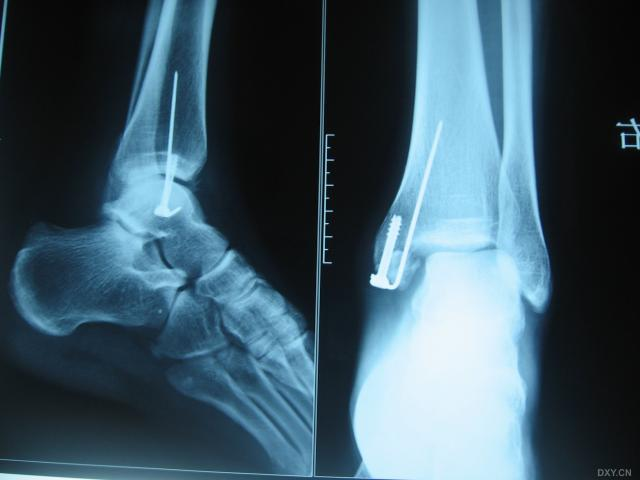

三、踝关节融合术

踝关节融合术于1879年被提出,多数学者迄今为止仍认为其是减轻患者疼痛和改善踝关节活动度的首选治疗方法。踝关节融合术是治疗终末期踝关节骨关节炎最可靠的方式,但是术后可能导致运动异常、步态改变及邻近关节关节炎等并发症。近年来,国外足踝外科专家越来越多地应用踝关节融合术来恢复足踝力线,重建非手术治疗效果欠佳的中后足和踝关节等严重畸形。据统计,50%的行踝关节融合术的骨关节炎患者在术后7~8年会出现后足周围关节炎。踝关节融合术后患者在不平路面行走存在困难,长时间活动甚至会疼痛,并且使距舟关节和跟骰关节的接触应力增加。接受踝关节融合术后,患者虽然会失去74%的矢状面活动度、70%的旋转活动度及77%的外翻活动度,但是治疗效果可靠,超过90%的患者对治疗结果满意。多数学者认为,踝关节的最佳固定位置是外翻5°~8°,外旋5°~10°,中立位背伸,向后偏移约5mm以提高跟骨力矩。关节镜下踝关节融合术是一种针对微小畸形的微创技术,与开放手术相比愈合时间更短。